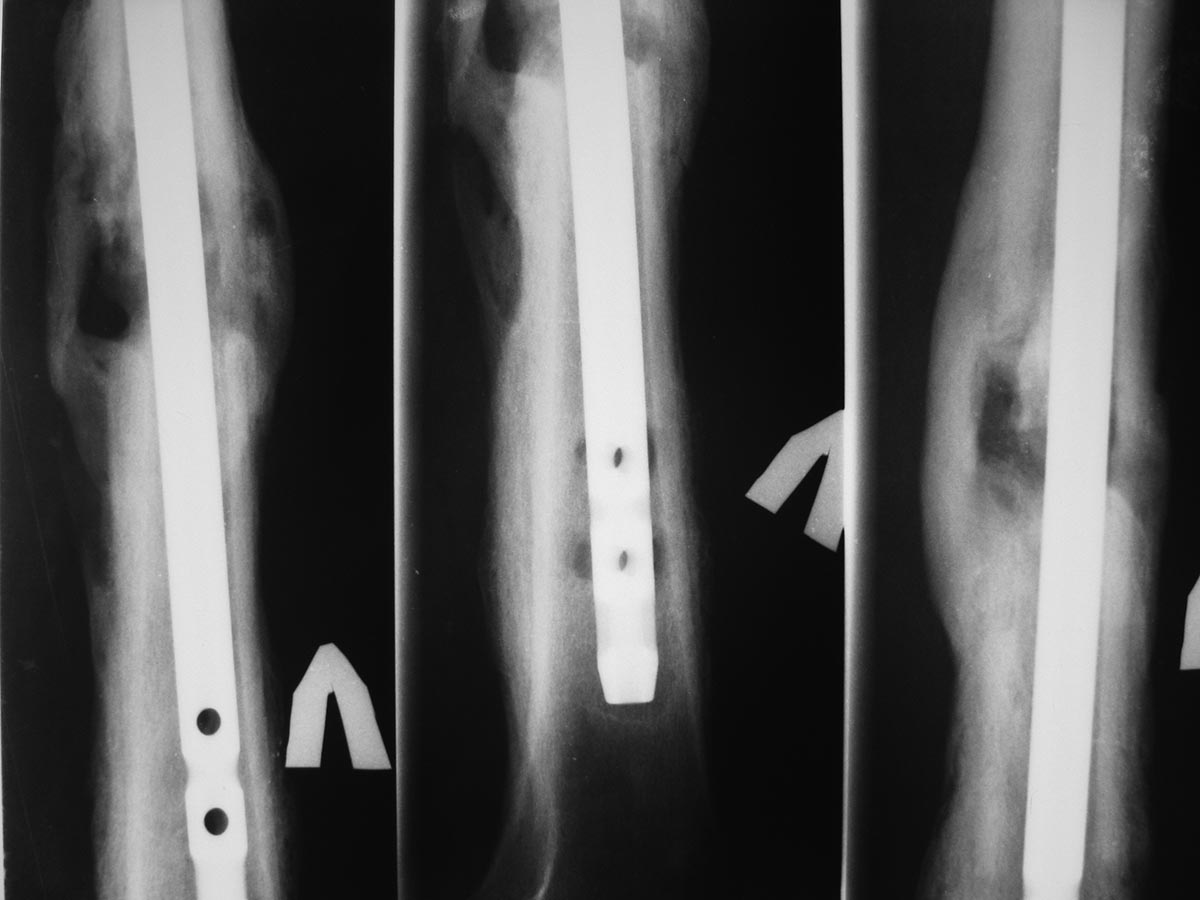

Спустя еще 4-5 мес обратился с жалобами на припухлость в области дистального блокирования. В поликлинике сделали снимки и, с подозрением на остеомиелит, оправили в стационар.

Сегодня: местно - без признаков инфекции. В области дистального блокирования припухлость плотно-эластичной консистенции. При пункции получить ничего не удалось. Лейкоциты 6,0; СОЭ - 22. СРБ-18. Температура в вечерние часы 37-37,2

Снимки представлены.